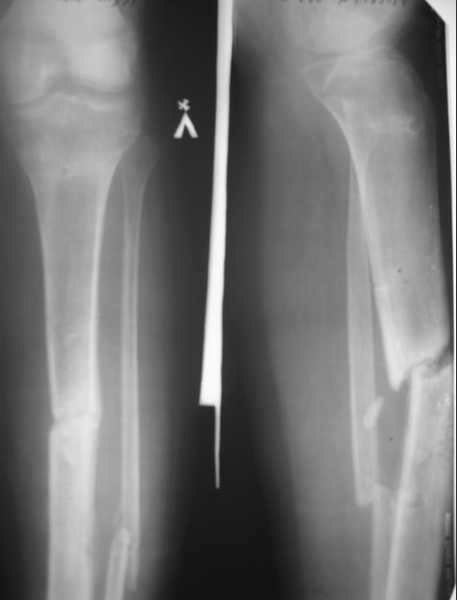

пациент 20 лет, травма в июне 2007 г. Открытый перелом костей левой

голени со смещением отломков. В этот же день выполнена ПХО открытого

перелома костей левой голени, фиксация в КДА по Илизарову. Раны заживали

вторичным натяжением. В январе 2008г. сняли аппарат, по причине

нестабильности, - гипсовая иммобилизация. На данный момент согласно

контрольным рентгенограммам и времени прошедшего с момента травмы

имеется нормо, гипотрофичный ложный сустав большеберцовой кости. Местно

- признаков воспаления не определяется. Лабораторные

показатели в пределах нормы.

Планирую: 1. Рассверлить канал риммерами до диметра 12 13 мм, и

выполнить остеосинтез блокированным канюлированным стержнем диметром 11

12 мм.